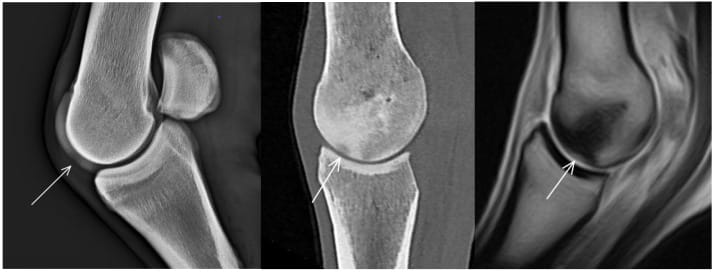

Lateromedial (flexed) radiograph, sagittal computed tomographic (CT) reconstruction and sagittal T1-weighted gradient echo magnetic resonance (MR) image (dorsal is to the left) of a metacarpophalangeal joint of a non-lame Thoroughbred yearling. There is a radiolucent/hypoattenuating/hyperintense lesion in the dorsal subchondral bone of the sagittal ridge of the third metacarpal bone (arrows), suggestive of osteochondrosis. Cone-shaped hyperattenuation/hypointense signal widening towards the lesion is evident in CT and MR images in the dorsal two-thirds of the bone.